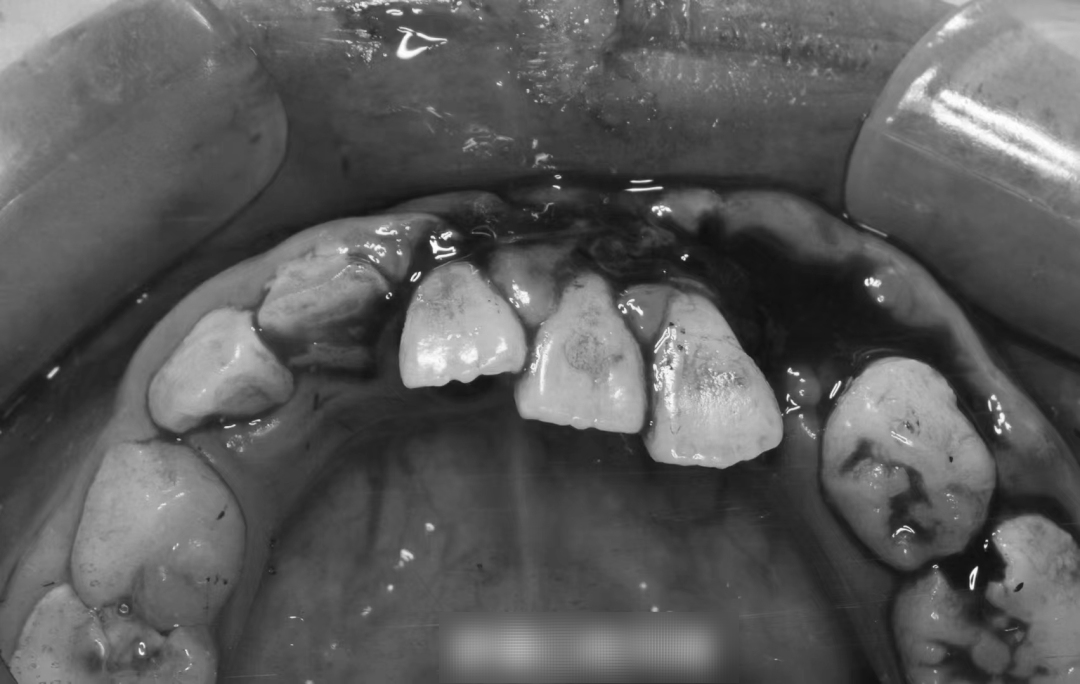

“我女儿说,骑电动车的是一名妇女,她被撞倒后对方问她有没有事,孩子当时有点疼,也被吓懵了,呆呆地说了句没事,对方竟直接走了。尽管路过的好心人建议该妇女给孩子买瓶水,看看嘴巴和牙齿,对方也没照做。”王先生气愤地说,他把孩子带到专业的牙科诊所拍了片子,两颗虎牙,一颗直接摔断了,另一颗被连根拔起不见了,三颗门牙牙根受损严重,需要矫正。